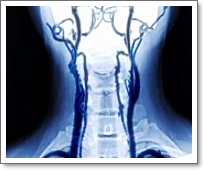

경동맥 초음파 검사

경동맥 초음파 검사란, 목에 위치한 경동맥(頸動脈)을 초음파로 촬영하여 혈관 내벽 상태, 혈류 흐름, 좁아진 부위(협착), 혈전 여부 등을 확인하는 비침습적 검사 방법입니다.이 검사는 초음파 탐촉자(프로브)를 목에 대고 실시간으로 혈관을 관찰하는 방식으로 이루어지며, 조영제나 방사선 없이도 안전하게 혈관 건강을 평가할 수 있다는 장점이 있습니다.특히, 뇌졸중(중풍) 위험을 사전에 확인하거나, 동맥경화 및 심혈관질환 위험 평가, 고혈압, 당뇨, 고지혈증 환자의 혈관 상태를 추적 관찰하는 데 유용하게 활용됩니다. 검사 시간은 보통 10~20분 정도이며, 통증이나 부작용이 거의 없어 정기적인 예방 검진으로도 매우 권장됩니다.